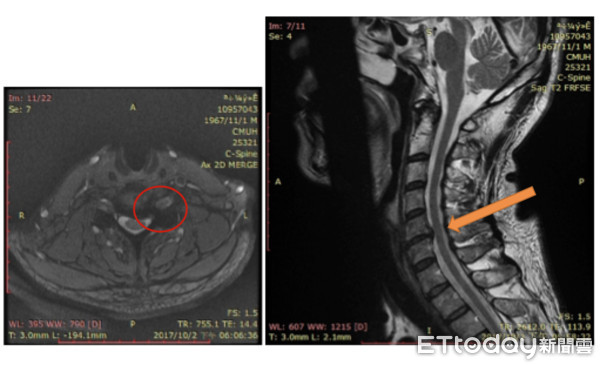

▲頸椎間盤成型手術是利用電離子汽化技術將突出椎間盤縮回,傷口像針孔一樣小。(圖/中國附醫提供)

中國附醫自2012年至2018年止,共幫53位患者完成椎間盤成型手術,除了何小姐外,還有一名45歲的保險業務員詹先生,車禍2週後左手突然舉不起來,磁振造影顯示頸部第五至六左側、三至四至五節右側有椎間盤突出,術後恢復良好,現已回到工作崗位。